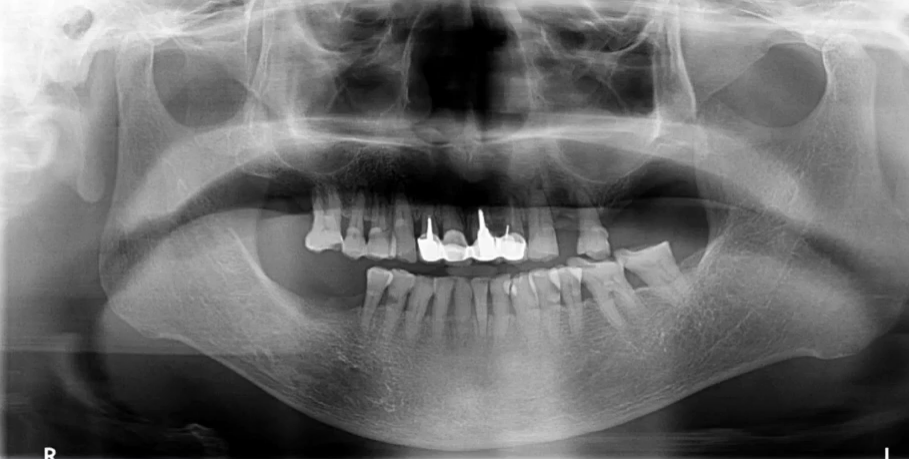

【病例5】

71岁,女性,右下颌后牙缺失要求种牙

曲断片:全面了解患者口腔情况

种植:缺牙位置、上颌窦、下颌神经管

牙周:牙槽骨、牙结石

牙体:龋坏、根尖炎、楔缺、合面磨耗

曲面断层片怎么看口腔精读 | 一次性教你看懂曲面断层片!_https://www.jmylbn.com_新闻资讯_第60张

上颌前牙区阴影:舌头位置不对→重拍?

下颌神经管显示不清:影响种植设计→进一步检查?

拍摄配合程度——年龄

初步诊断及预判:结合临床检查,哪些重点检查;影像经验,14、15,12、21,23,11、22